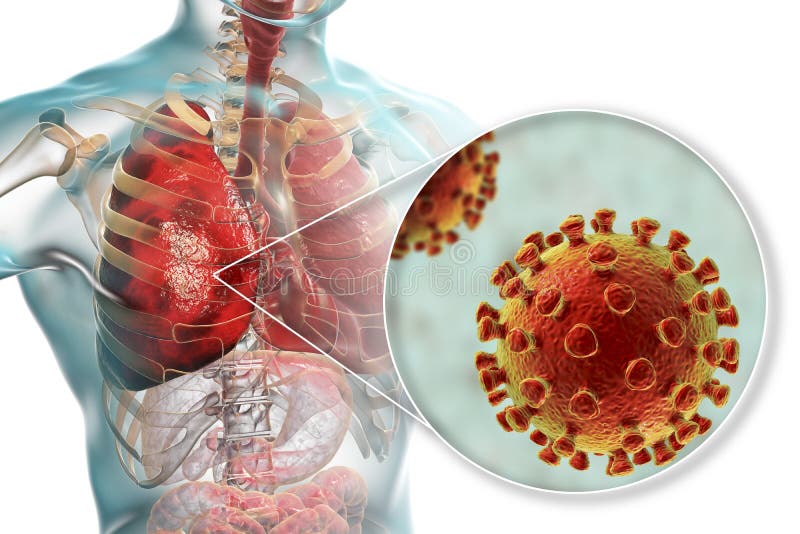

Фотографии бактерий, вызывающих бактериальные пневмонии у животных

Раздел: Другие животные